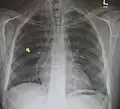

Pneumomediastinum is uncommon and occurs when air leaks into the mediastinum. The diagnosis can be confirmed via chest X-ray showing a radiolucent outline around the heart and mediastinum or via CT scanning of the thorax.

Pneumomediastinum with angel wing sign[15]